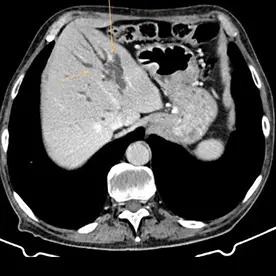

Durchführung einer kontrastmittelgestützten CT-Untersuchung des Abdomens in arterieller und venöser Kontrastmittelphase. Neben einer reizlosen Cholezystholithiasis zeigt sich ein massiv erweiterter D. pancreaticus bis zur Papille und diffuse zystische Pankreasläsionen, teils mit Verkalkungen (Bild 4 und 5) mit dem Hauptbefund im Pankreasschwanz angrenzend an die linke Nebenniere; kein Nachweis solider Anteile (Bild 1). Zusätzlich wurden mehrere kalkdichte Konkremente im Pankreas nachgewiesen, die sich vorwiegend im Bereich des Caput befinden. Keine Lymphadenopathie. Keine metastasensuspekten Herdsetzungen. Als weitere Nebenbefunde wurden eine parenchymverschmälerte Niere rechts und der V.a. auf ein Nebennierenadenom geäußert.

Verdacht auf eine intrapankreatische muzinöse Neoplasie (IPMN) vom Hauptgangtyp. Auch die intra- und extrahepatischen Gallenwege zeigen sich deutlich dilatiert (Bild 2 und 3).